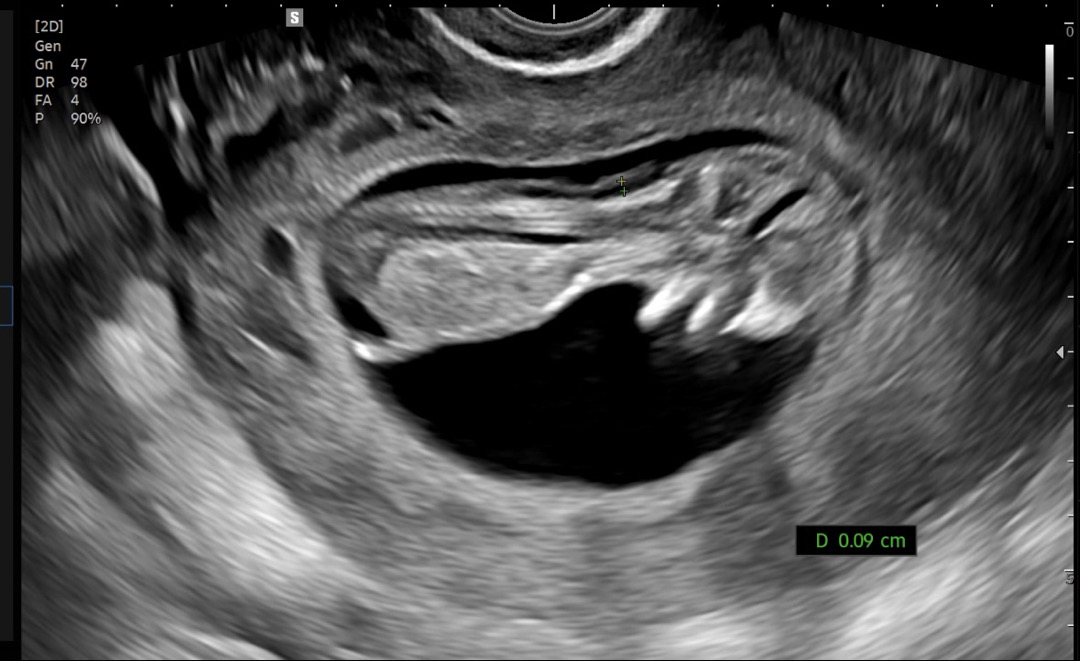

11주4일 각도법 봐주세요!

초음파보는 내내 계속 움직여서 거꾸로 매달려있는 오리같지만 아들일까요 딸일까요?!